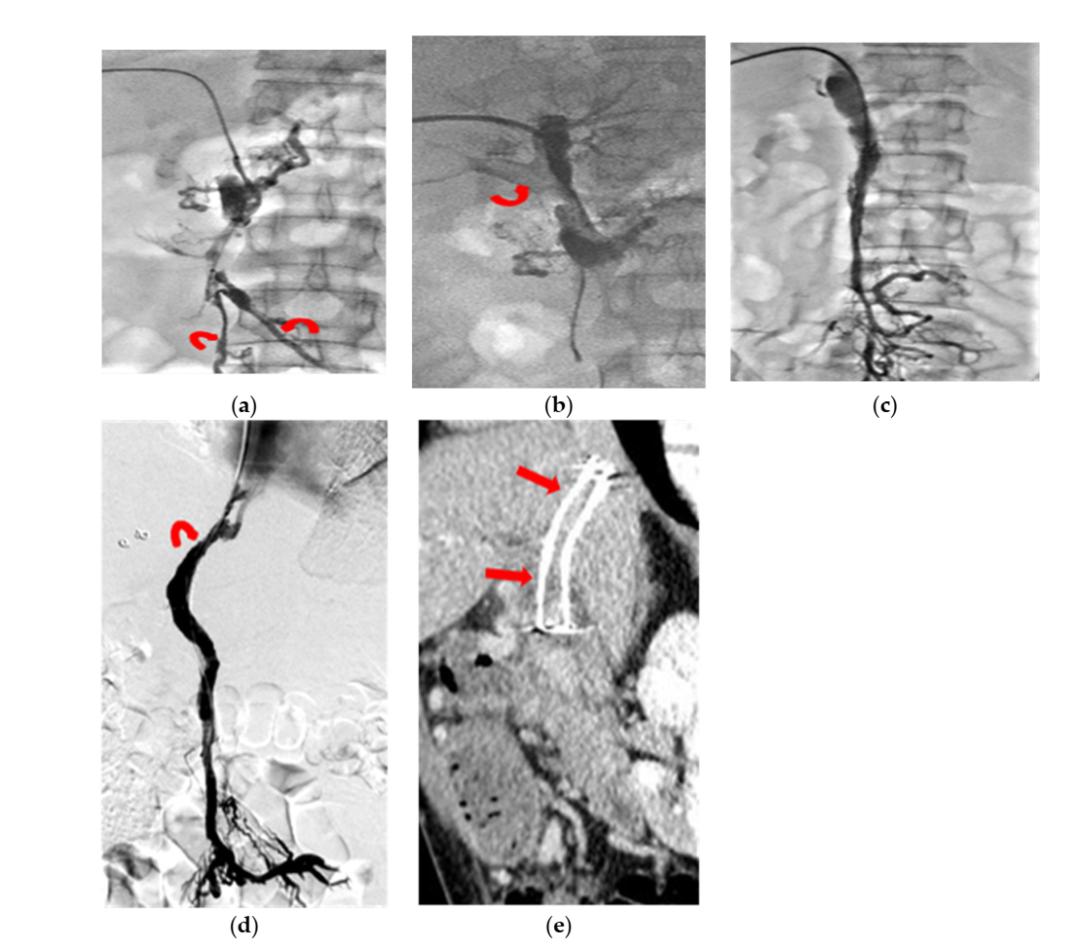

(图源自文献)

一例慢性PMVT急性加重患者,男,44岁,主诉为腹痛22天。

a

经皮肝穿刺PV造影显示:弥漫性PMVT累及肝内PV周围小静脉,未累及肠系膜周围小静脉(曲线箭头)。

b

经皮肝穿刺PV造影显示:经连续输注UK、反复导管抽吸,PV右支(曲线箭头)部分再通。

c

经皮肝穿刺PV造影显示:MV和PV主干几乎完全再通,因无后继血栓溶解而肝内PV未显影。

d

第10天行TIPS(曲线箭头)以降低流出阻力。

e

3个月随访CT(斜矢状位图像重建)显示:PMV再通且TIPS分流道通畅。